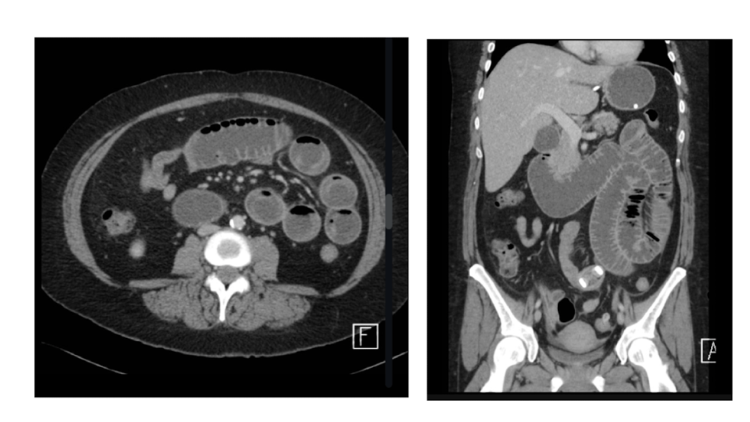

Phase + pathology?

• In PVP as there is opacification of

the portal vein and the liver is also

opacified

• Path = small bowel obstruction

• Small bowel as its characterised by

the ridged lines

• Bowels are dilated and we can’t see

any gas patterns distal to the obstruction.